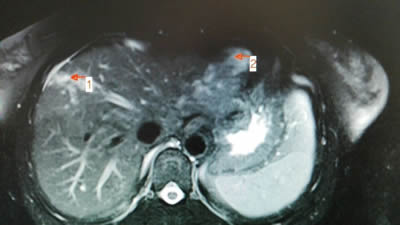

术前影像学发现右肝7×5cm的肝血管瘤 术前影像学发现左肝5×4cm的肝血管瘤

术中:DSA下肝左右叶血管瘤栓塞治疗后成像(见图标1、2) 半年后返院复查,肝左右叶血管瘤基本消失(见图标1、2)